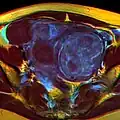

-

A very large (9 cm) fibroid of the uterus which is causing pelvic congestion syndrome as seen on CT -

A very large (9 cm) fibroid of the uterus which is causing pelvic congestion syndrome as seen on ultrasound -

A relatively large submucosal leiomyoma; it fills out the major part of the endometrial cavity. -